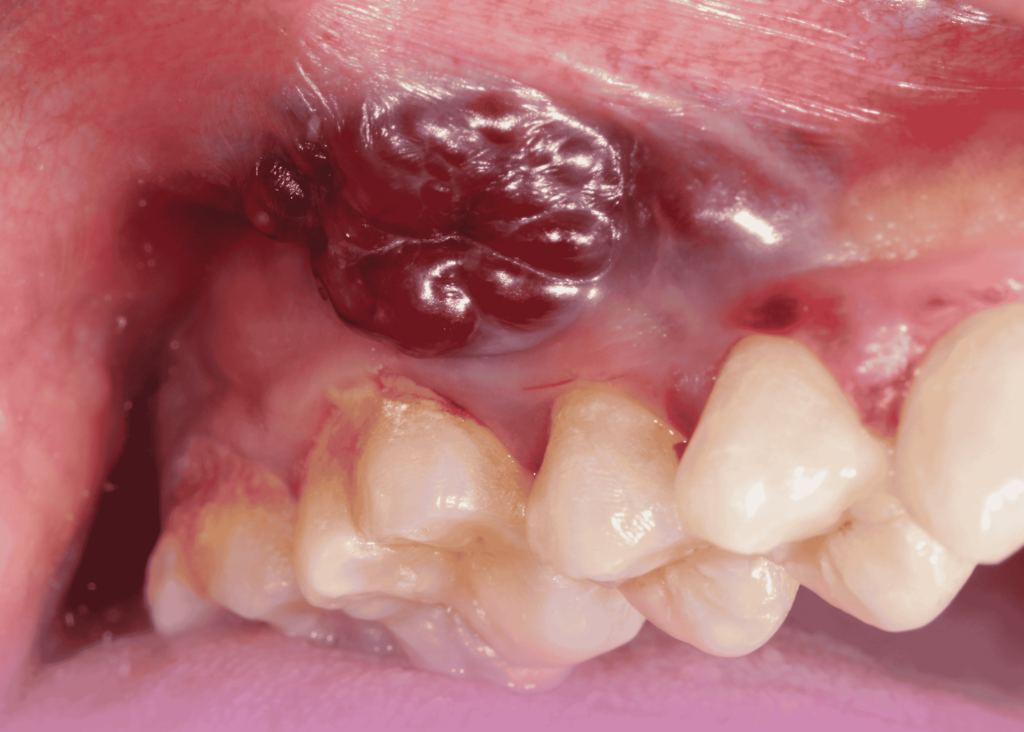

سرطان دهان به مجموعه ای از بدخیمی ها اطلاق می شود که بافت های دهان، زبان، لثه، کف دهان، سقف دهان و گاهی لب ها را درگیر می کنند. شایع ترین نوع آن کارسینوم سلول سنگفرشی است که از سلول های پوششی دهان منشا می گیرد. این سرطان می تواند به سرعت رشد کند و در صورت عدم تشخیص به موقع به غدد لنفاوی گردن و سایر اندام ها گسترش یابد.

شناخت علائم هشداردهنده سرطان دهان می تواند به مراجعه زودهنگام به پزشک کمک کند. از جمله این علائم می توان به زخم هایی که بیش از دو هفته بهبود نمی یابند، لکه های سفید یا قرمز روی مخاط دهان، درد یا بی حسی مداوم و دشواری در بلع اشاره کرد. افراد سیگاری باید نسبت به این نشانه ها حساس تر باشند.

گاهی تغییر در صدا، لق شدن غیر طبیعی دندان ها یا تورم در ناحیه گردن نیز می تواند نشانه گسترش بیماری باشد. نادیده گرفتن این علائم و نسبت دادن آنها به مشکلات ساده دهانی می تواند تشخیص را به تاخیر بیندازد. آگاهی و اقدام به موقع نقش کلیدی در نجات جان دارد.